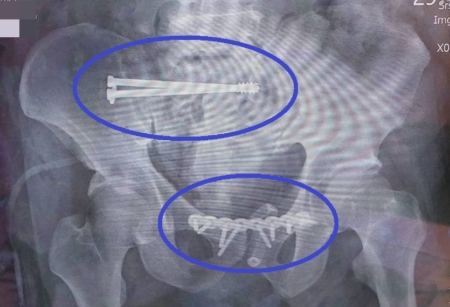

大千綜合醫院骨科主任范姜治澐表示,傷者送至急診時,第一時間即啟動外傷小組團隊共同處理。因傷者下背及右大腿疼痛無法活動,加上瀕臨休克狀態,因此先以骨盆固定帶予以固定,並給予靜脈輸液及輸血來穩定生命徵象,再立即由放射科醫師進行骨盆腔血管攝影及栓塞止血,並安排於加護病房做後續照護及觀察。所幸,傷者止血後生命徵象穩定,且沒有其他器官損傷,但因骨折位移較多,需要手術復位固定,所以隔天即接受骨折復位鋼板鋼釘固定手術,術後三天轉入一般病房進行復健治療,並於一週後順利出院。

范姜治澐主任進一步說明,在台灣每年約有200例骨盆骨折,其中可分為因骨質疏鬆造成的脆弱性骨盆骨折,以及因重大外力造成的創傷性骨盆骨折。嚴重的骨盆骨折常合併有身體多處骨折、神經血管損傷或其他生殖泌尿系統之多重外傷,在治療上須同時與其他科別如一般外科、影像診療科、泌尿科等等,通力合作共同治療病人。由於骨盆構造複雜,又有許多重要器官、神經及血管,手術不易且風險極高,對於醫療團隊是一個很大的挑戰。若發生骨折粉碎或傷及髖臼,更會大大增加手術困難度,即使積極治療,仍可能造成坐骨神經損傷,或是日後產生股骨頭壞死、創傷性關節炎等後遺症,需要進行後續的人工髖關節置換。

大多數長輩因骨質疏鬆造成的骨盆骨折,因傷害力道不大,多屬於穩定型骨折,不需接受手術治療,以一般保守治療3個月後即可恢復一般活動。此次的病人是由高處墜落,骨折嚴重位移且年紀大、骨質較為疏鬆,不論是急救過程、手術治療、後續照護,都考驗著醫療團隊的經驗以及技術,透過密切的配合以及即時處理,才能讓病人獲得較好的預後。